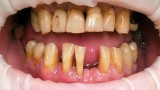

Jedną z popularniejszych metod stabilizacji zębów rozchwianych jest ich szynowanie. Metoda ta, wspierająca inne metody leczenia, jest powszechnie stosowana. Jednym z najnowocześniejszych materiałów wykorzystywanych w stomatologii do szynowania zębów jest taśma poliaramidowa. W opisanym przypadku autorzy pracy przedstawiają sposób uproszczenia całej procedury i ograniczenia ryzyka popełnienia błędu, szczególnie w sytuacji całkowitej utraty zęba. Uzyskano to dzięki zastosowaniu indeksu wykonanego z przezroczystego silikonu.

One of the more popular methods of stabilising loose teeth is to splint them. This method, aiding other methods of treatment, is generally used. One of the most modern materials used in dentistry for splinting teeth, is polyamide tape. In the case described the authors show how to simplify the whole procedure and limit the risk of making a mistake, particularly in the situation of total loss of one tooth. This was achieved thanks to the use of an index made out of transparent silicone.